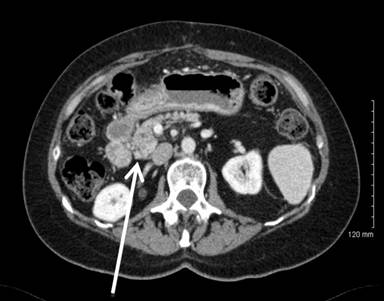

A Fifty nine-year-old otherwise healthy Caucasian female presented to an outside hospital in November 2010 with right upper quadrant pain and an enlarged gallbladder on ultrasound. She was taken to the operating room where the planned laparoscopic cholecystectomy was aborted given the identification of a segment 6 liver lesions. Biopsy demonstrated metastatic adenocarcinoma with a suspected gallbladder primary. Computerized tomography (CT) scan showed a giant gallbladder measuring about 18 cm (Figure 1). A large mass (11.0x3.1 cm) was visualized within the gallbladder with no clear evidence of invasion into liver, cystic duct or proximal common bile duct. Two hypodense, right lobe liver lesions were also present with the dominant mass measuring 2.5x1.8 cm in segment 6 (Figure 2). Preoperative tumor markers including cancer antigen 19-9 (CA 19-9) and carcinoembryonic antigen (CEA) were normal.

Figure 1. Preoperative CT scan demonstrating giant gallbladder. |

Figure 2. Preoperative CT scan demonstrating metastatic segment 6 liver lesion. |

Figure 7. Metastatic papillary gallbladder adenocarcinoma in the uncinate process of the pancreas. |